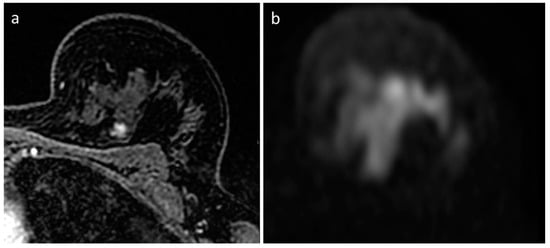

- Amornsiripanitch, N.; Bickelhaupt, S.; Shin, H.J.; Dang, M.; Rahbar, H.; Pinker, K.; Partridge, S.C. Diffusion-weighted MRI for Unenhanced Breast Cancer Screening. Radiology 2019, 293, 504–520. [Google Scholar] [CrossRef]

- Trimboli, R.M.; Verardi, N.; Cartia, F.; Carbonaro, L.A.; Sardanelli, F. Breast cancer detection using double reading of unenhanced MRI including T1-weighted, T2-weighted STIR, and diffusion-weighted imaging: A proof of concept study. AJR Am. J. Roentgenol. 2014, 203, 674–681. [Google Scholar] [CrossRef]

- Baltzer, P.A.; Benndorf, M.; Dietzel, M.; Gajda, M.; Camara, O.; Kaiser, W.A. Sensitivity and specificity of unenhanced MR mammography (DWI combined with T2-weighted TSE imaging, ueMRM) for the differentiation of mass lesions. Eur. Radiol. 2010, 20, 1101–1110. [Google Scholar] [CrossRef] [PubMed]

- Baltzer, P.A.T.; Bickel, H.; Spick, C.; Wengert, G.; Woitek, R.; Kapetas, P.; Clauser, P.; Helbich, T.H.; Pinker, K. Potential of Noncontrast Magnetic Resonance Imaging with Diffusion-Weighted Imaging in Characterization of Breast Lesions: Intraindividual Comparison with Dynamic Contrast-Enhanced Magnetic Resonance Imaging. Investig. Radiol. 2018, 53, 229–235. [Google Scholar] [CrossRef]